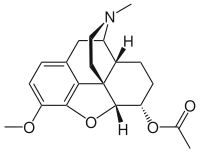

- Esters of morphine opiates: slightly chemically altered but more natural than the semi-synthetics, as most are morphine prodrugs, diacetylmorphine (morphine diacetate; heroin), nicomorphine (morphine dinicotinate), dipropanoylmorphine (morphine dipropionate), desomorphine, acetylpropionylmorphine, dibenzoylmorphine, diacetyldihydromorphine;[261][262]